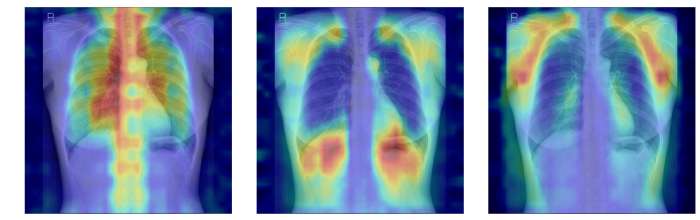

¡ã ÈäºÎX¼±¿¡¼­ ÆÄ¿îµ¥ÀÌ¼Ç ¸ðµ¨ÀÌ °ñ´Ù°øÁõ ÆÇµ¶À» À§ÇØ ÁÖ¸ñÇÑ ¿µ¿ªÀ» ½Ã°¢È­ÇÑ À̹ÌÁö

¿¬±¸ÆÀÀº ¿©±â¿¡ ´õÇØ AI°¡ ½ÇÁ¦·Î ¾î¶² »À¸¦ ±Ù°Å·Î »ï¾Æ ÆÇ´ÜÇÏ´ÂÁö±îÁö È®ÀÎÇÒ ¼ö ÀÖµµ·Ï ¡®¼³¸í °¡´É¼º¡¯ Æò°¡ ü°è¸¦ ¼³°èÇß´Ù. »À¸¦ ¸ðµÎ °¡¸° »óÅ¿¡¼­ ƯÁ¤ »À ºÎÀ§¸¦ Ãß°¡ÇØ ¼º´ÉÀÌ ¾ó¸¶³ª Çâ»óÇÏ´ÂÁö È®ÀÎÇÏ´Â ¡®Â÷´Ü ºÐ¼® ¹æ½Ä(¥Äbone)¡¯°ú Grad-CAMÀ¸·Î ³ªÅ¸³­ AIÀÇ ÁÖ¸ñ ¿µ¿ªÀÌ ½ÇÁ¦ »À À§Ä¡¿Í ¾ó¸¶³ª ÀÏÄ¡ÇÏ´ÂÁö¸¦ °è»êÇÏ´Â ¡®À¯ÀǼº Áöµµ ¹æ½Ä(IoUbone)¡¯À» ÅëÇØ, AI°¡ ÀÓ»óÀûÀ¸·Î Áß¿äÇÑ »À ±¸Á¶¸¦ ±Ù°Å·Î ÆÇ´ÜÇÏ´ÂÁö¸¦ Á¤·®ÀûÀ¸·Î °ËÁõÇß´Ù.

±× °á°ú, DINOv2 ¸ðµ¨¿¡ LoRA ¹æ½ÄÀ» Àû¿ëÇÑ ¸ðµ¨ÀÌ AUC 0.93(95% CI 0.920.94)·Î °¡Àå ³ôÀº ¿¹Ãø ¼º´ÉÀ» º¸¿´´Ù. ÀÌ ¸ðµ¨Àº »À ±¸Á¶ Ȱ¿ëµµ°¡ °¡Àå ³ô°í, ÁÖ¸ñ ¿µ¿ªÀÇ Å¸´ç¼º¿¡¼­µµ ¿ì¼öÇØ, ¿¹Ãø·Â°ú ¼³¸í °¡´É¼ºÀÌ ±ÕÇü ÀÖ°Ô È®º¸µÈ ÃÖÀû ¸ðµ¨·Î Æò°¡µÆ´Ù.